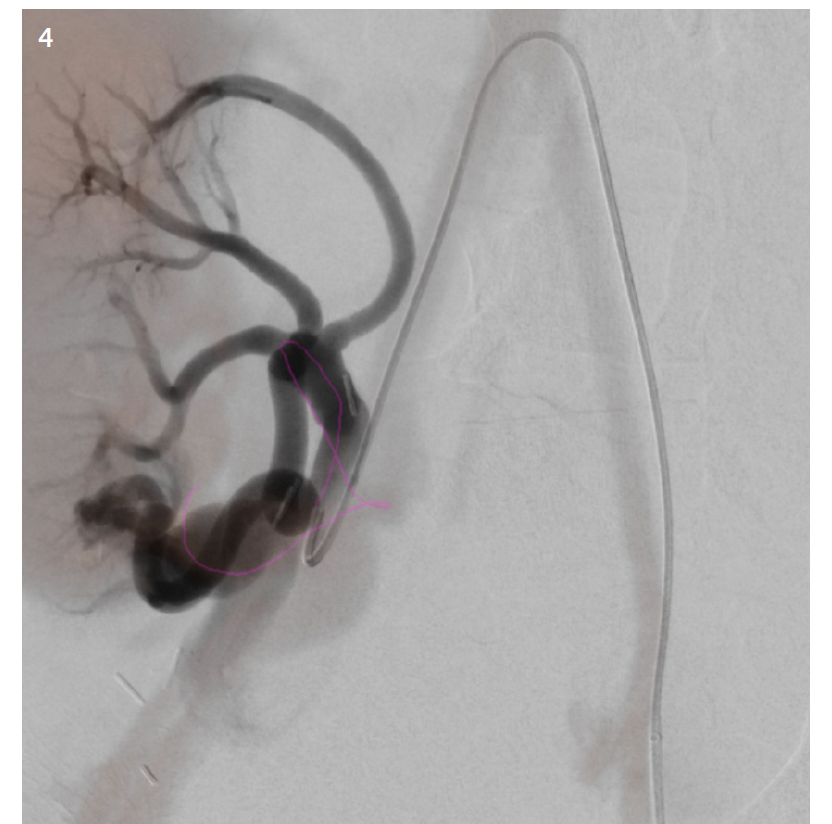

In pediatrics, MR and CT datasets are mainly used for fusion to assist with intraprocedural guidance and road mapping. As with most things in pediatrics, its use is currently limited. It is, however, an area of interest that is growing among the community. Sometimes patient vascular anatomy is complex; other times, patient size makes navigating even normal anatomy difficult. Though most interventionalists would be able to perform a complicated case without assistance, the datasets have potential to help decrease patient radiation and contrast dose in the hands of even the most skilled users. This may be able to be accomplished through use of the patient’s prior cross-sectional imaging to create 3D roadmaps on the day of treatment. While it may not be a “perfect” one-to-one recreation of the patient’s anatomy, the roadmap created and overlaid on live fluoroscopy is often more than sufficient (Figure 1). In complex cases, the roadmap created will at the very least give the interventionalist a better approximation of where a tortuous vessel’s origin might be in the 3D space (Figure 2). And if the interventionalist has a better idea of the vessel origin, they may be able to select it faster, thus limiting patient radiation and contrast dose. And while the same software can be used for even more advanced techniques such as organ segmenting, it is straightforward to use. It doesn’t matter how useful or “nifty” you think something is if it is unreliable and cumbersome to implement. Once the interventionalist understands Siemens’ simple and intuitive workflow, use of prior imaging in this manner is something that can easily be done with little effort and time. The other thing to keep in mind is with the simplified workflow; if whatever overlay was created using the patient’s prior imaging is not helpful or is a hinderance, it can easily be turned off. While it may seem counterintuitive, the ability to easily turn off an advanced feature if it is not serving its purpose is just as important as to not waste time in the suite doing unnecessary troubleshooting.